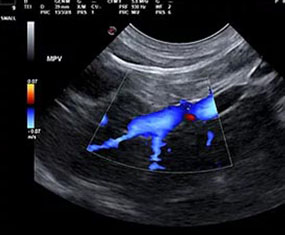

We elected to offer not only abdominal, cardiac and small parts ultrasound but also provide interventional procedures necessary to fulfill the diagnostic pathway. By doing so, we are capable of scanning a patient, working with attending veterinarians to assess patients for biopsy or aspiration and then collecting any samples that may be required to accurately diagnose and address the underlying concern.

At RVUS we have chosen industry leading equipment from vendors with reputable and proven track records in the industry. From the front lines to your final report it is imperative that the equipment and the user provide images that equip the specialists with the highest level of quality and reproducibility to confidently provide an accurate interpretation of the sonogram.

This, in turn, provides you with additional tools to arrive at a diagnosis and prognosis and to enhance the care model for your patient and confidence with your client. Our team of professionals with decades of ultrasound experience encourage the use of ultrasound as a leading route to non-invasively assess organs and pathology in question. To cover that spectrum, a variety of transducers are essential, all with different characteristics.

Whether your patient is 100 lbs or 10 lbs, take comfort in knowing your sonographer is capable of generating images that are sensitive and specific to the clinical concerns.